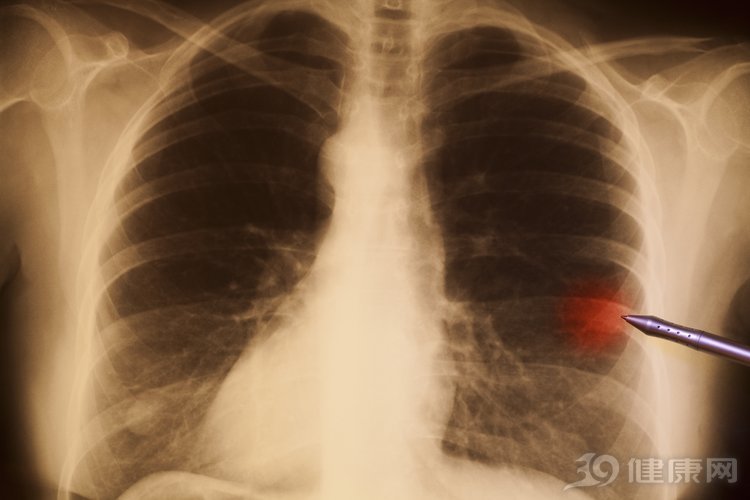

肺癌位列我国十大恶性肿瘤榜首,发病率和死亡率都很高。在肺癌早期,往往没有明显的症状,到了有症状发生的时候,多数是癌细胞扩散,肺癌到了晚期。

晚期肺癌扩散,会有什么症状?

除了以上三个明显症状之外,还有很多疑似是肺癌扩散的症状,而且肺癌扩散到不同的部位,引起的症状也不同。如扩散到骨骼,会引起骨痛、骨折、瘦腿无力等;扩散到肝,会引起皮肤发黄、腹部肿胀、皮肤发痒等。

肺癌症状有很多种,也因人而异,所以如果意识到有异常,需要到医院进一步诊断后才能确定。